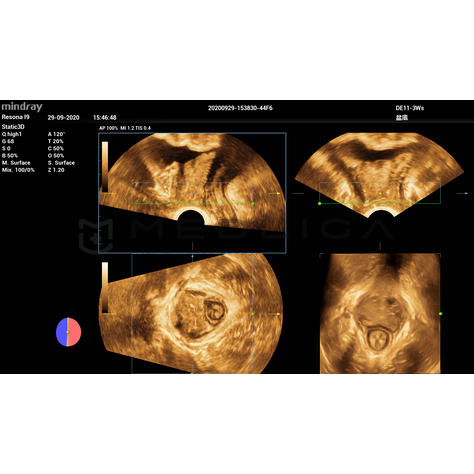

Smart Pelvic - новое решение, позволяющее значительно упростить диагностическую процедуру и свести к минимуму время исследования функций мышц тазового дна. Благодаря чрезвычайно простому пользовательскому интерфейсу, программа генерирует стандартную систему координат и автоматически просчитывает все связанные измерения в течение нескольких секунд.